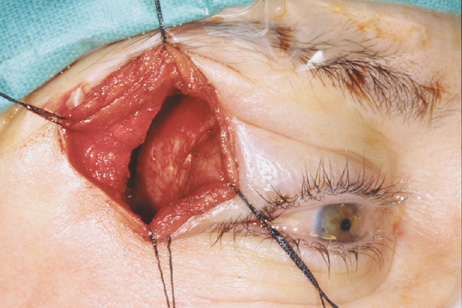

Fig. 6. Lateral orbitotomy through upper eyelid skin crease A. Photo demonstrating right globe ptosis present for more than 2 years. B. Axial CT scan showing a well outlined oval lesion in the lacrimal gland

fossa. C. Coronal CT showing lesion pushing globe inferiorly. D. Skin crease excision marked for lateral orbitotomy. E. Lateral orbital rim exposed. Bone cuts made above frontozygomatic suture

and at zygomatic arch. F. Lateral wall removed. Subperiosteal space exposed. Hard tumor could be

palpated in area of lacrimal gland. G. Benign mixed tumor of lacrimal gland removed. H. Bone sutured into place. I. Skin crease closed. |